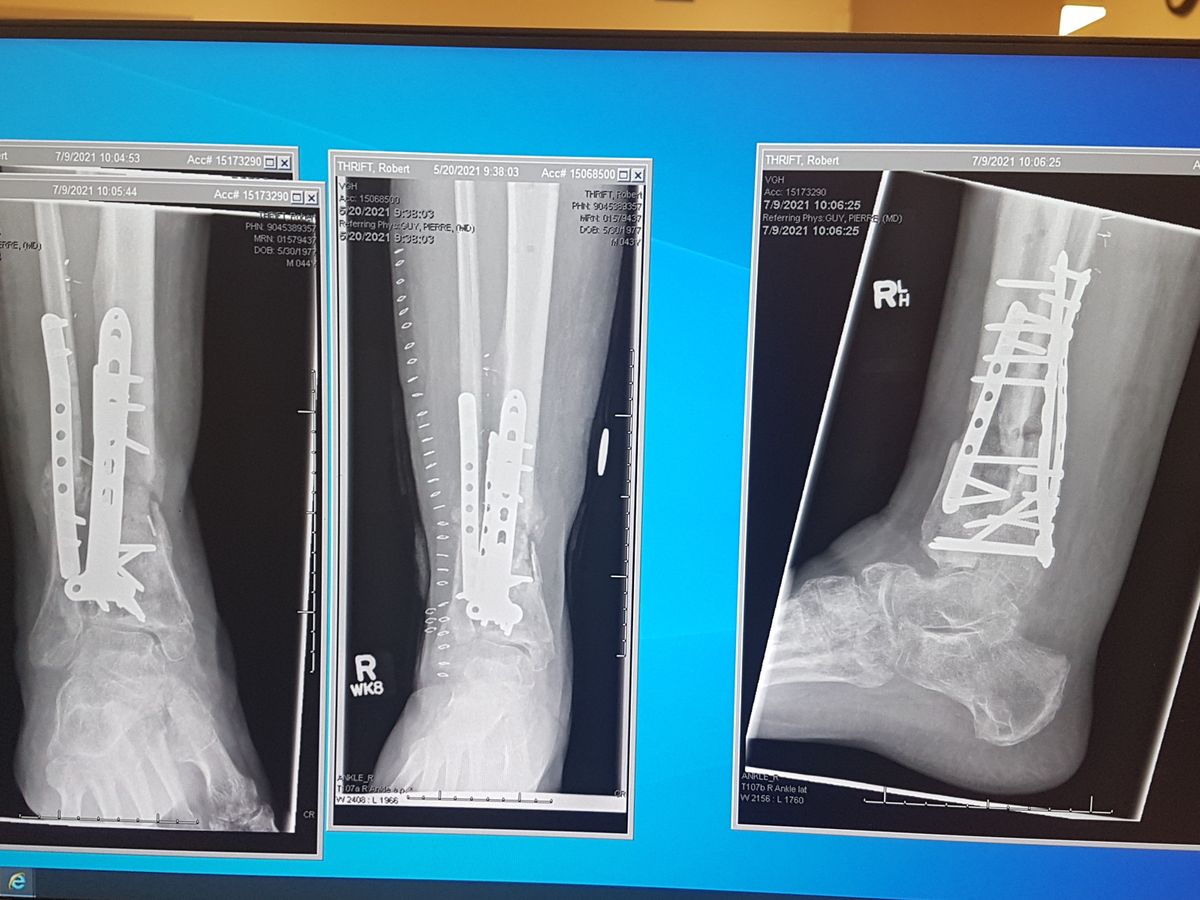

On July 10th 2020 I had a workplace accident that shattered my tibia and fibula on my right leg, effectively breaking it right off. After 2 surgeons and 5 surgeries I was able to keep my foot, but have been on Worksafe Benefits and unable to work for the last 2 years and counting.